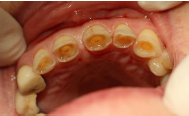

Es gibt weitere Erkennungsmerkmale der Zähne wie z. B. erworbene Strukturveränderungen. Dazu zählen Abrasionen, Attritionen und Erosionen.

Bei der Abrasion handelt es sich um Zahnhartsubstanzverlust durch Zahn-Zahn-Kontakte + ein zusätzliches Medium. Abrasionen entstehen oft durch Zähnepressen oder Zähneknirschen, welche meist in der Nacht infolge von Stressfaktoren auftreten.

Bei der Attrition handelt es sich um Zahnhartsubstanzverlust durch Zahn-Zahn-Kontakte.

Bei der Erosion handelt es sich um Zahnhartsubstanzverlust durch Säureeinwirkung.